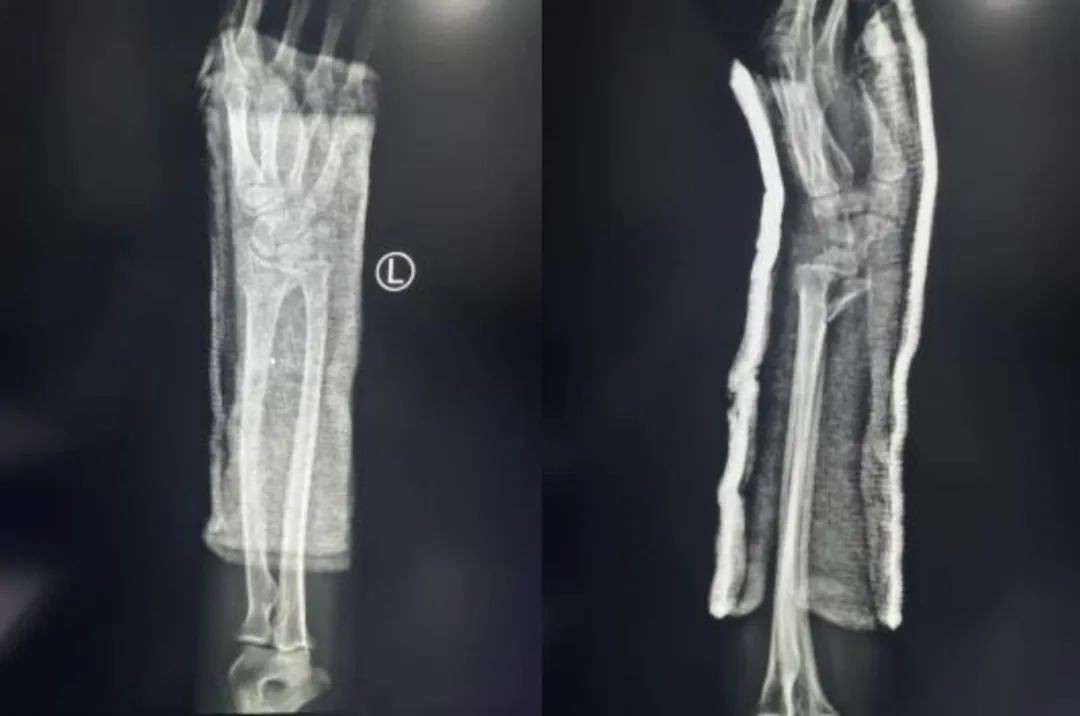

Primer ②